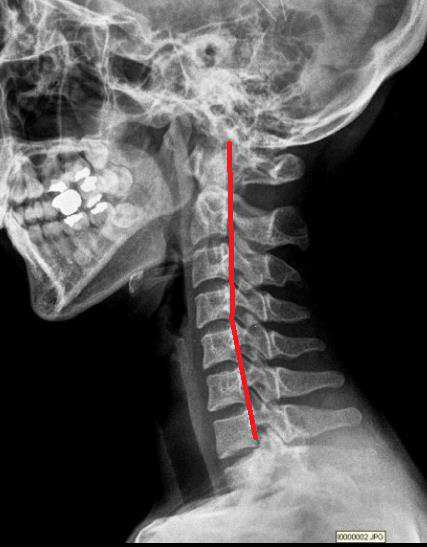

일자목과 디스크를 진단 받은 환자를 추나요법으로 치료한 사례

20대 여성이 목디스크로 인해 만성적인 목의 통증과 어깨 통증으로 내원하였으며 추나요법으로 호전된 치료사례

일자목으로 목의 통증을 호소하는 환자분으로 허리 역시 일자 허리 인데 같이 목이 아프다고 해서 목만 치료해서는 안되고 같이 치료해야 좋아질 수 있습니다.